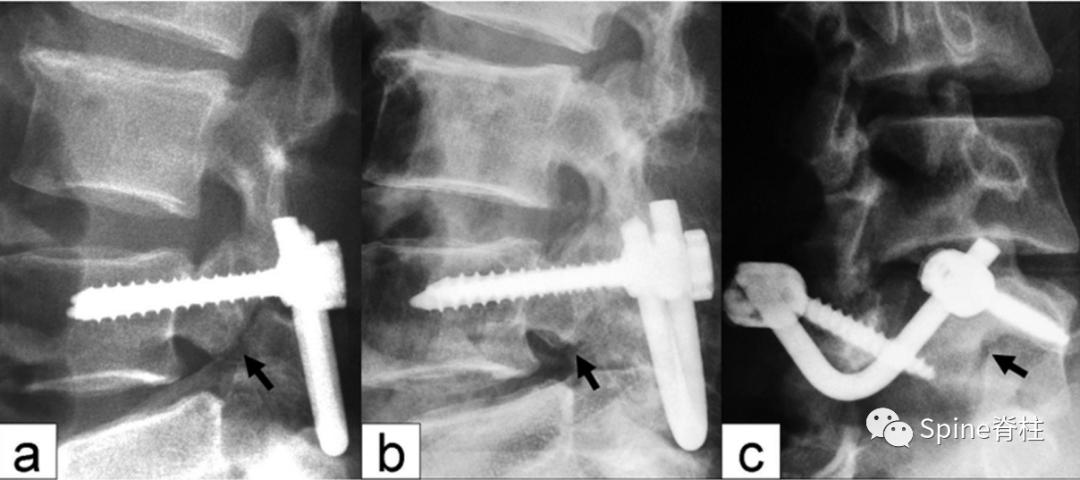

4. 拉力螺钉+张力带固定方法

我的博导谭军教授于2002年提出拉力螺钉张力带固定方法,是Buck螺钉法和Scott接线法的联合。